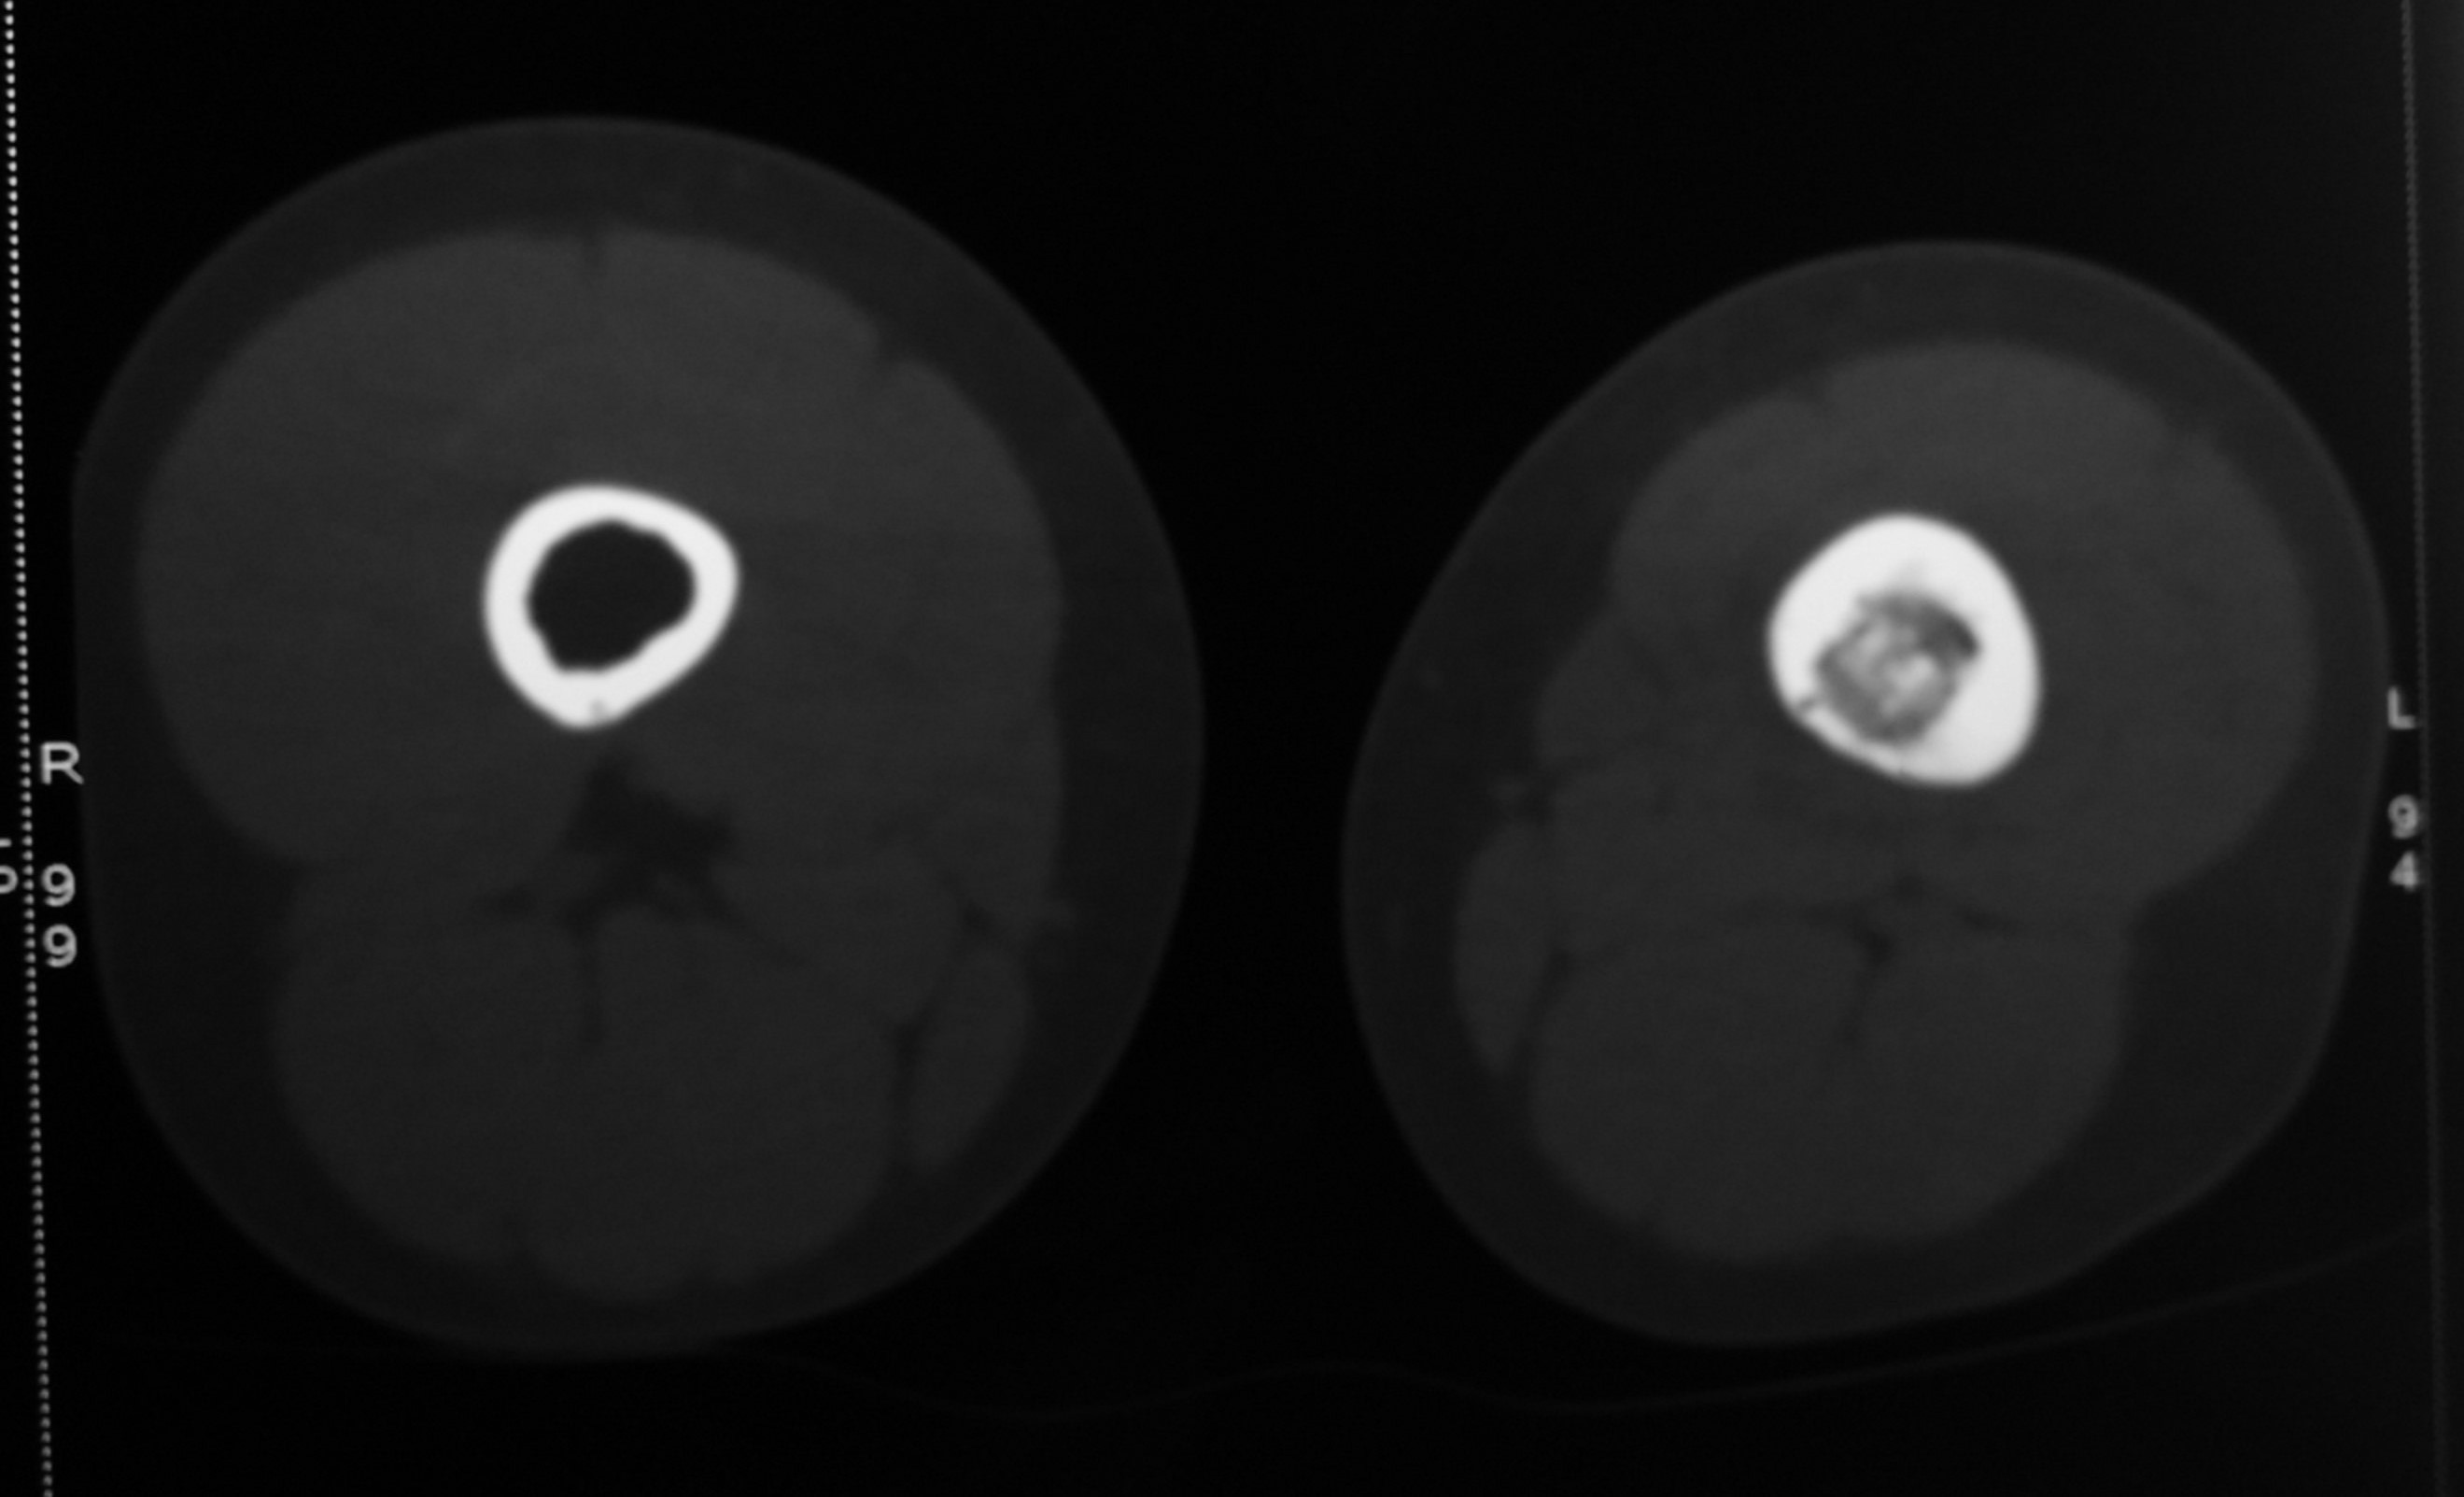

CT-scan was done to further evaluate the lesion. It confirmed the diagnosis based on the typical features.

The CT-scan also showed muscle atrophy of the left thigh muscles compared to the right thigh.